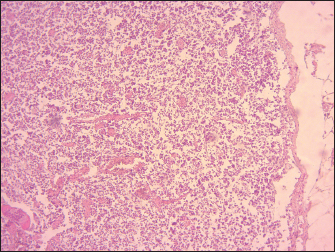

The lymphoid follicles in Peyer’s patches exhibited destruction, characterized by lympholysis (Fig. 6). MLNs showed severe congestion, hemorrhage, swelling, and depletion of lymphoid cells (Fig. 7). Additionally, other lesions are marked by the depletion of lymphocytes in the spleen, and histopathological changes in the heart, including congestion and hemorrhages. The thymus showed severe depletion of lymphocytes and severe congestion (Fig. 8). Furthermore, the liver showed severe congestion and hemorrhage with hepatocyte atrophy accompanied by the expansion of the sinusoidal spaces. The kidney exhibited slight glomerular atrophy, significant necrosis, and loss of epithelium in the renal tubules.

The results of the histopathological study revealed lympholysis and loss of lymphoid cells in Peyer’s patches, spleen, thymus, and lymph nodes of lambs affected by PPR.

The lymphoid depletion observed in the present study can be attributed to a combination of direct viral cytopathic effects. These include the replication of PPRV within lymphocytes, which results in direct damage and death of these cells, and the immunosuppression resulting from lymphoid depletion predisposes the host to secondary infections, which can further destroy and deplete lymphoid tissues.

Fig. 7. Sheep, MLNs demonstrating severe lymphoid depletion mainly in the cortex with congestion and severe hemorrhage (100X, H&E).

Fig. 8. Sheep, thymus, severe congestion and depletion of lymphoid cells (40X, H&E).